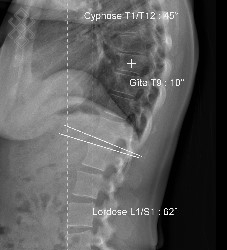

TéléRadiographie du Rachis en totalité